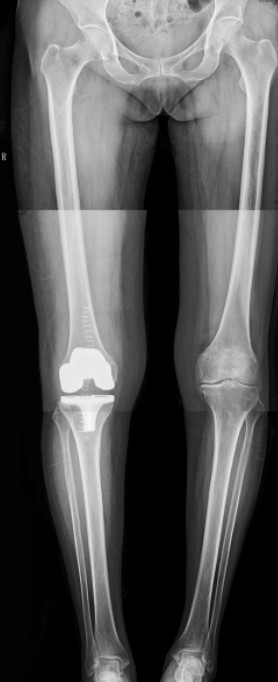

病例一:患者女性,72歲。主因“左膝疼痛伴活動(dòng)受限4年”入院?;颊咝g(shù)前走路時(shí)明顯跛行,連續(xù)行走最多50米需要坐下休息。

患者術(shù)前              患者術(shù)后

患者術(shù)后全長